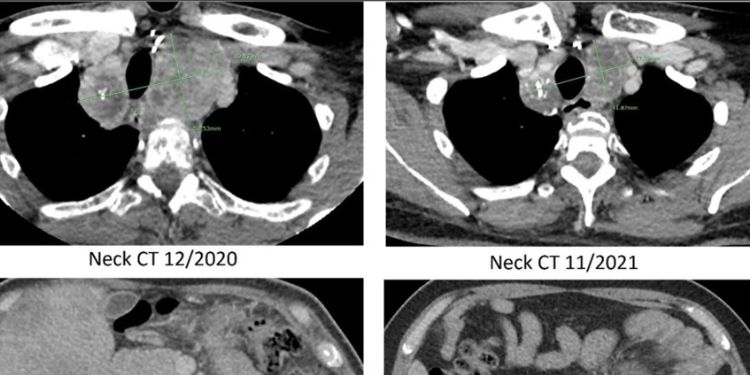

RET 898-901Del mutant, a variant of unknown significance, has a durable response to Pralsetinib in a Medullary Thyroid Carcinoma patient

DOI: 10.14302/issn.2574-4496.jtc-23-4722

Published on 30 Sep 2023

Read the full article